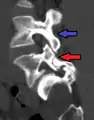

Anterolisthesis L5/S1. Blue arrow normal pars interarticularis. Red arrow is a break in pars interarticularis.

Magnetic Resonance Imaging (MRI)

Magnetic resonance imaging is the preferred advanced imaging technique for evaluation of spondylolisthesis.[30] Preference is due to effectiveness, lack of radiation exposure, and ability to evaluate for soft tissue abnormalities and spinal canal involvement.[30][31] MRI is limited in its ability to evaluate fractures in great detail, compared to other advanced imaging modalities.[32]